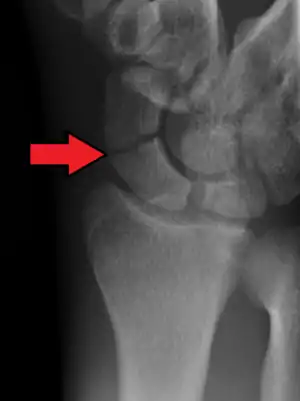

Radiolucency around a 12 days old scaphoid fracture that was initially barely visible.[12]